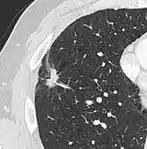

Calcifications and popcorn-like appearance, conferring a diagnosis of hamartoma.[9]

• In case of calcifications, a popcorn-like appearance indicates a hamartoma, which is benign.[3]